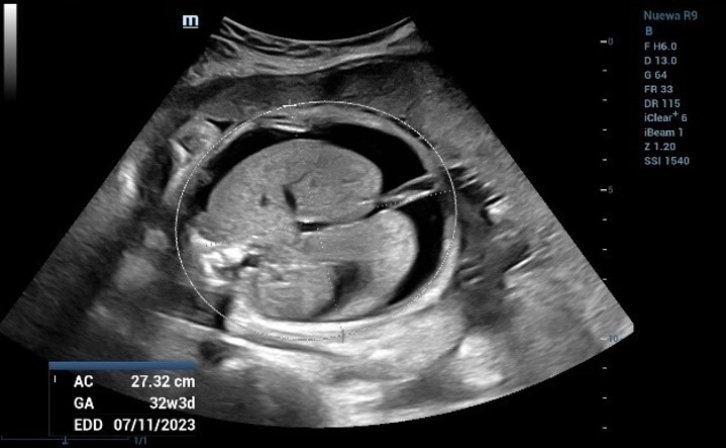

The measurement of Biparietal Diameter (BPD) (Figure 1) and Femur Length (FL) (Figure 2) demonstrated a close approximation to the actual gestational age. However, when assessing the Abdominal circumference (AC), it was observed that the measured gestational age exceeded the actual gestational age due to the presence of fluid accumulation around the fetal abdomen (Figure 3).

Fetal Biometric Measurements: Abdominal Circumference (AC)

Figure 3 Fetal Biometric Measurements: Abdominal Circumference (AC). AC is one of the basic biometric parameters used to assess fetal size

Abdominal circumference (AC) is one of the basic biometric parameters used to assess fetal size. AC, along with BPD, HC, and FL, are calculated to provide an estimation of fetal weight. In the second trimester, this can be extrapolated to estimate gestational age and the expected date of delivery (EDD).

In Figure 8, there is significant fluid accumulation observed around the fetus in both the abdominal cavity (ascites) and thorax (pleural effusion).